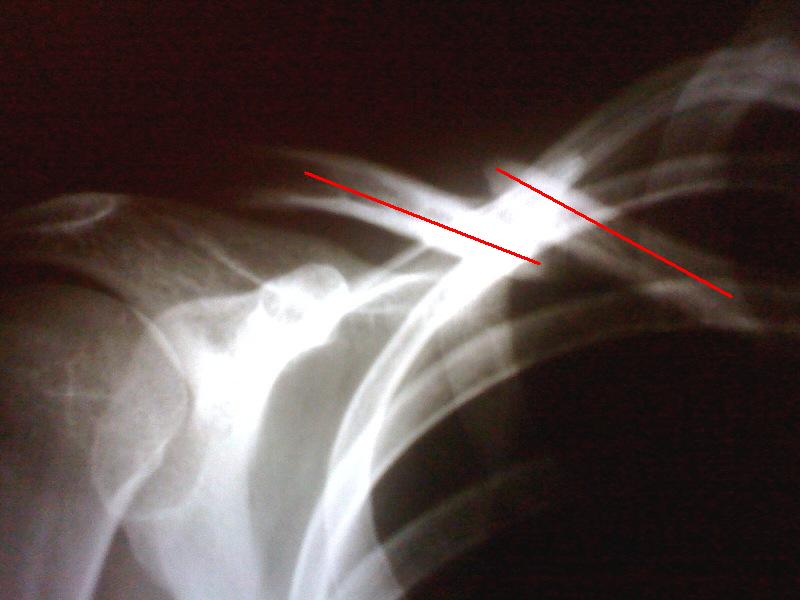

Vergleich nach 4 Monaten

Links das Bild vom 02.08.2009, frisch nach dem Unfall. Rechts das von gestern. Ich hatte nochmal einen Termin bei einem weiteren Arzt. Jetzt habe ich eine Überweisung zum Uniklinikum in der Tasche und noch ein weiterer Arzt darf über das Schlüsselbein philosophieren. Ich denke dann fällt auch die Entscheidung ob noch operiert wird oder nicht…